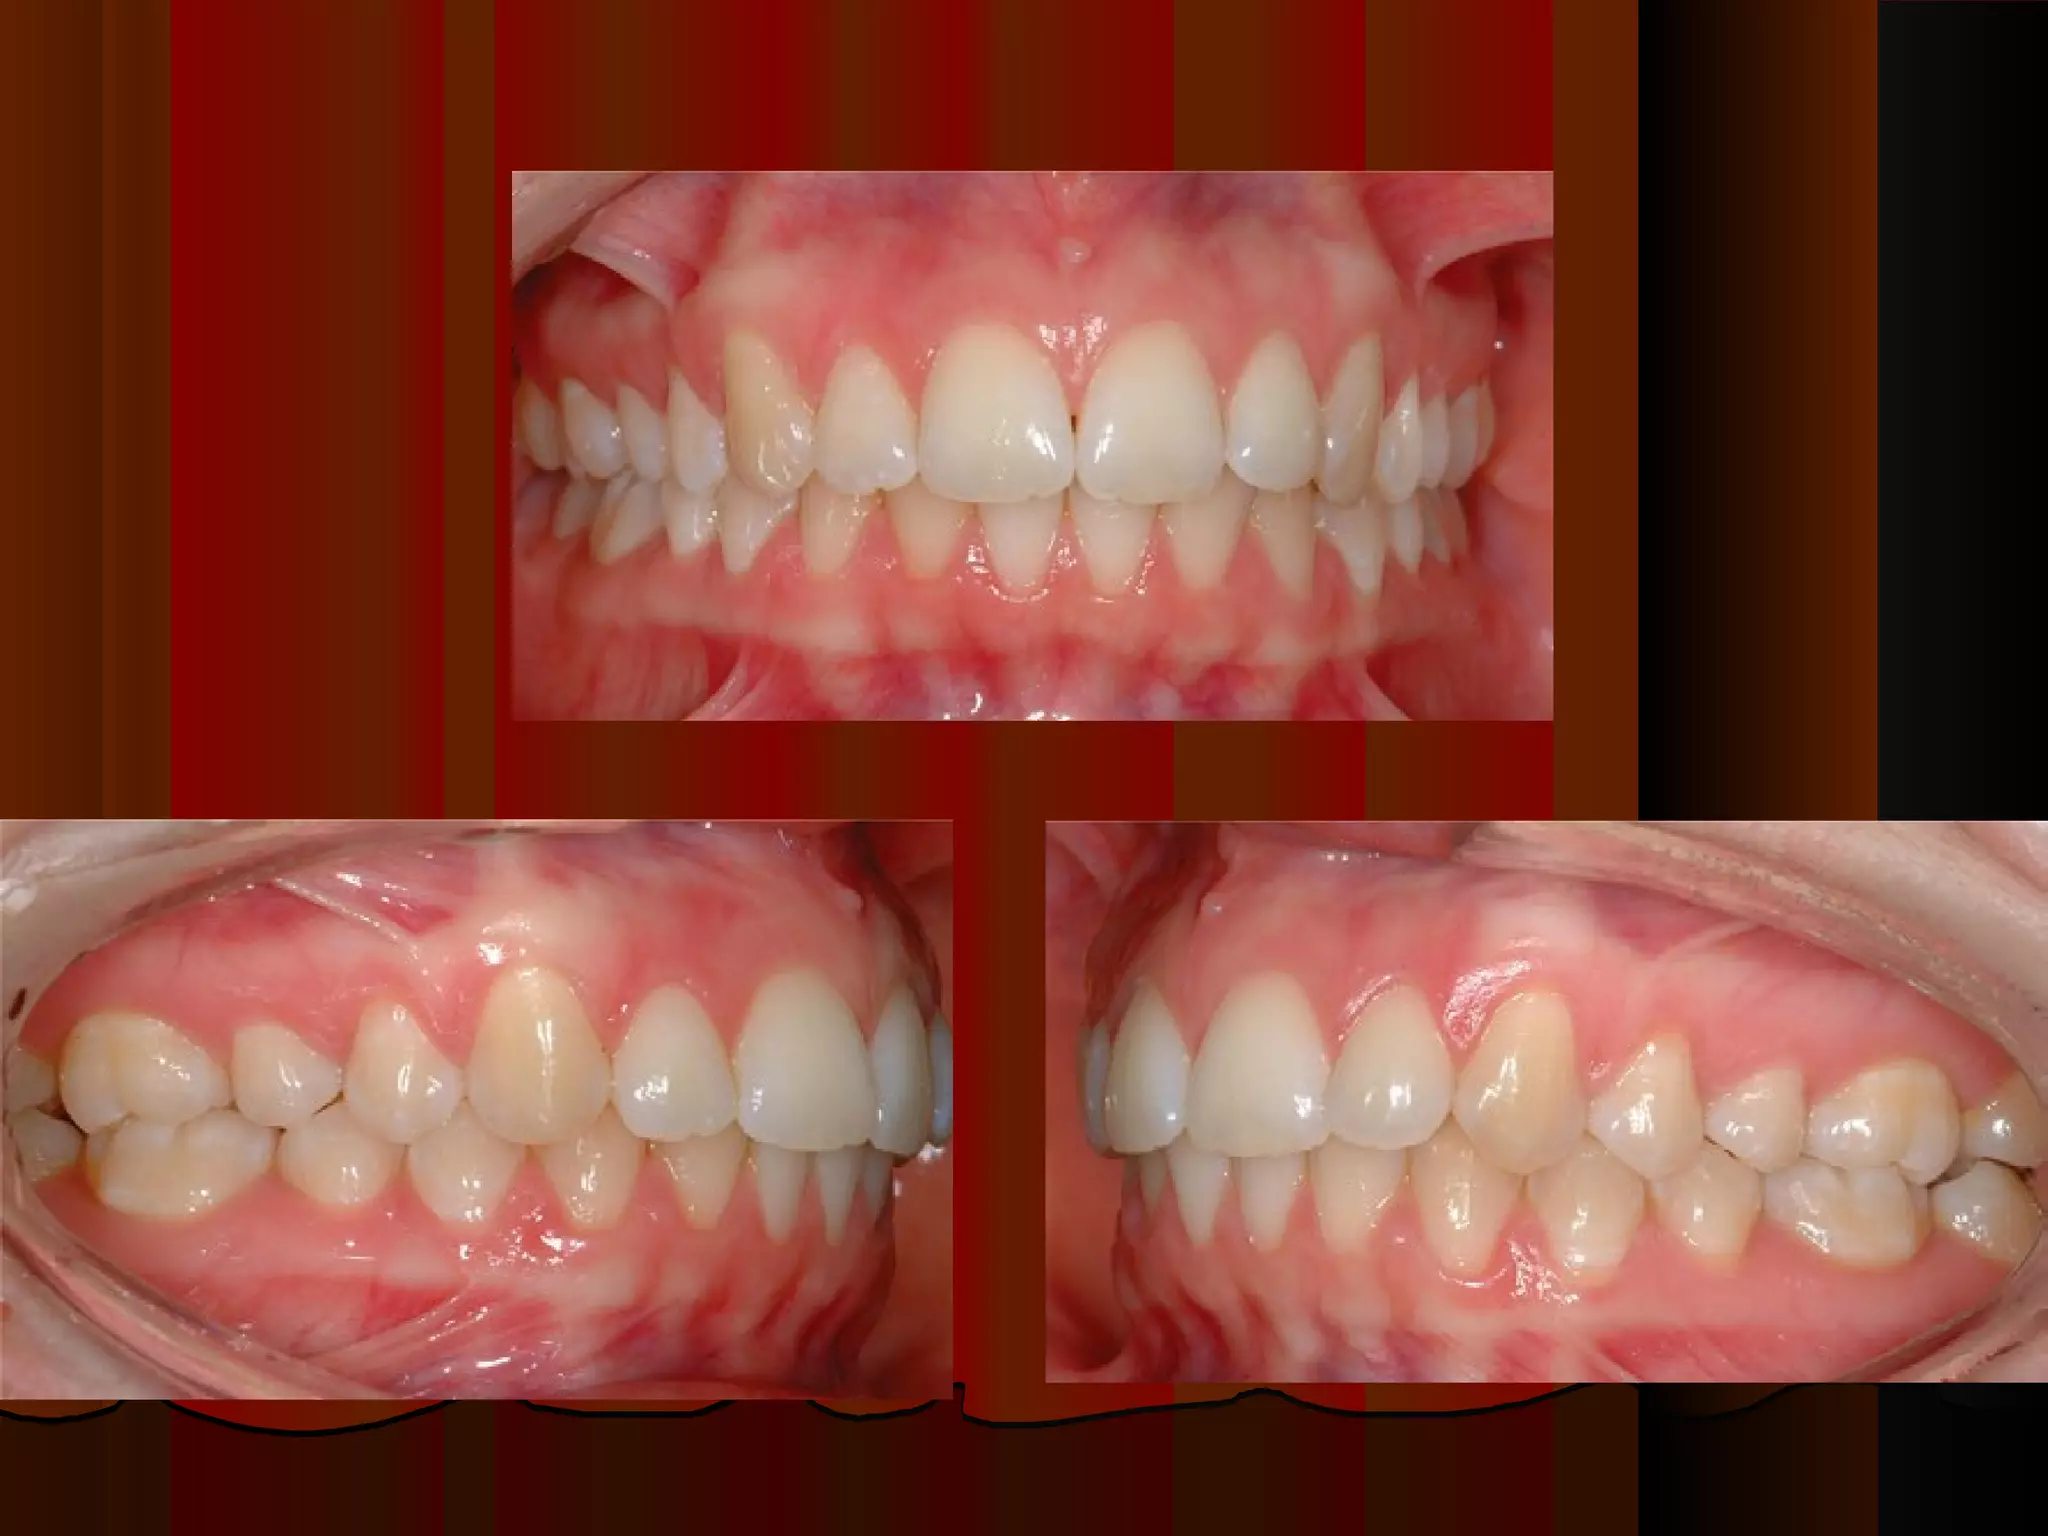

CLASS III MALOCCLUSION.

The upper first permanent molar occludes distal to the

buccal developmental groove of the lower first permanent

molar.

Line of occlusion not specified.

CLASS III MALOCCLUSION. Theupper first permanent molar occludes distal to the buccal developmental groove of the lower first permanent molar. Line of occlusion not specified.